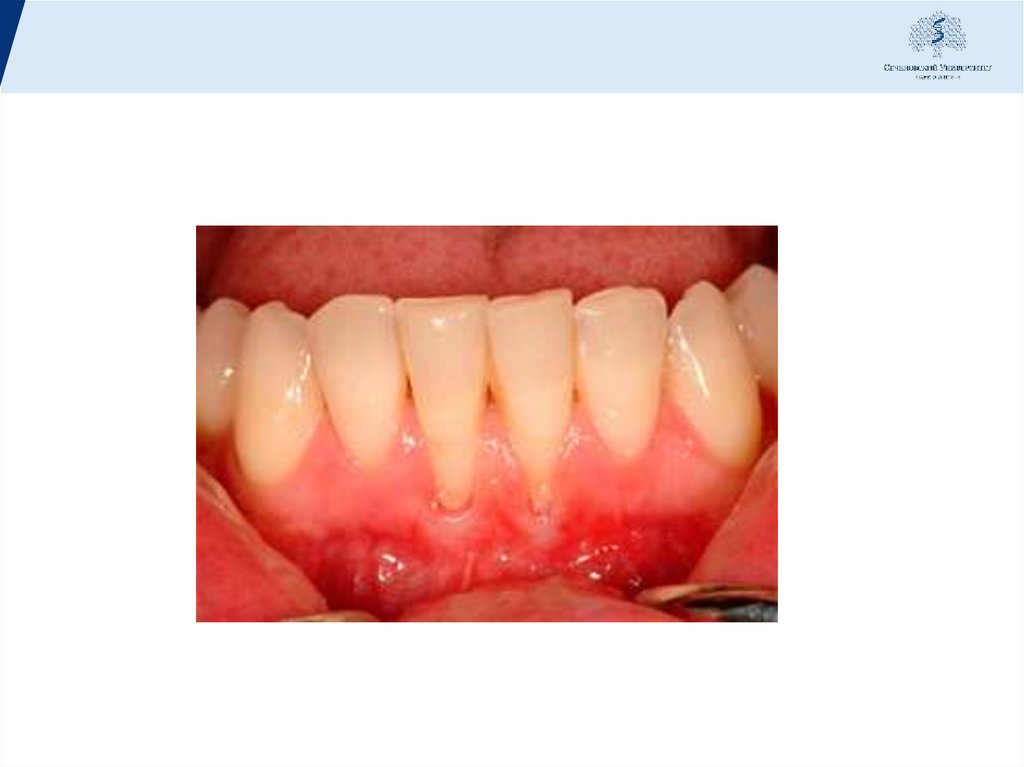

39. Временное шинирование

• Временные протезы изготавливают с целью восстановить

дефекты зубных рядов и шинировать имеющиеся ,позволяет

устранить травматическое воздействие патологической

подвижности,обеспечивает равномерное распределение

жевательного давления между пародонтом зубов

включенных в шину, создает покой пораженным тканям и

способствует повышению эффективности патогенетической и

симптоматической терапии.

40. В шину включают все зубы, обеспечивая иммобилизацию по дуге.

Временные шины

изготавливают из

пластмассы. Различают

• капповые шины

• оральные

• вестибуло-оральные

многозвеньевые

Капповые шины охватывают окклюзионную часть

коронок зубов, их применение связано с завышением

окклюзионной высоты.

Пластмассовые шины - каппы, армированные

металлической или неметаллической арматурой и

временно фиксированные, обеспечивают наилучший

шинирующий эффект, одновременно позволяют

восстановить дефекты зубного ряда и улучшить

внешний вид пациента.

Вестибуло-оральные шины (круговые) покрывают

только часть вестибулярной поверхности зуба, не

мешают смыканию антагонистов и не оттесняют

десневой край.

43. Технология наложения шины:

1.Предварительная абразивная обработка поверхности зубов для создания ретенционных пунктов.

2.Протравливание поверхности зубов.

3.Нанесение бонда на поверхность зубов.

4.Поэтапное прикладывание ленты к зубному ряду с заведением в межзубной промежуток и

засвечиванием поверхности.

5.В завершение шина покрывается тонким слоем композита с последующей полировкой. При

изготовлении шины, из гигиенических соображений, необходимо оставлять открытыми

придесенные промежутки между зубами.